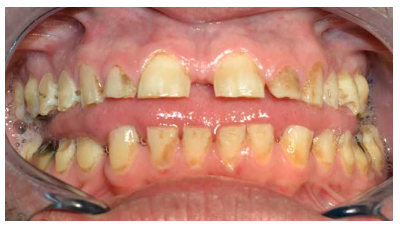

En la bibliografía se describe con detalle los defectos del esmalte que presentan los pacientes diagnosticados del síndrome de Morquio. Estos defectos son una característica aparentemente constante en la enfermedad y, por lo tanto, hace necesaria las visitas al odontólogo para su control evitándose problemas mayores. Dichos defectos consisten en un esmalte anormalmente delgado, que es áspero debido a los numerosos hoyos diminutos y a una superficie irregular. La delgadez del esmalte da como resultado una forma alterada y decoloración de los dientes que, añadido a los diastemas interdentales, provocan alteraciones en la oclusión. Aparte de estos defectos, el esmalte es histológicamente normal y tiene una dureza y radiodensidad normales. El tratamiento odontológico de los pacientes con MPS-IV requiere colaboración multidisciplinar, debido a que las manifestaciones orales de la enfermedad pueden aparecer a cualquier edad, resultando en ocasiones tedioso para el paciente y complicado para el profesional. Especial mención merecen las terapias utilizadas como tratamiento sintomático de la enfermedad, así como el manejo de la vía aérea en el caso de intervenciones bajo anestesia general o sedación para tratar ciertas patologías del territorio bucomaxilodental.

The enamel defects presented by patients diagnosed with Morquio syndrome are described in detail in the bibliography. These defects are an apparently constant feature in the disease and, therefore, make visits to the dentist necessary for their control, avoiding major problems. These defects consist of an abnormally thin enamel that is rough due to numerous tiny holes and an irregular surface. The thinness of the enamel results in an altered form and discoloration of the teeth, which added to the interdental diastemas, cause alterations in the occlusion. Apart from these defects, the enamel is histologically normal and has a normal hardness and radiodensity.

Dental treatment of patients with MPS-IV requires multidisciplinary collaboration, because the oral manifestations of the disease can appear at any age, being sometimes tedious for the patient and complicated for the professional. Special mention should be made of the therapies used as a symptomatic treatment of the disease, as well as the management of the airway in the case of interventions under general anesthesia or sedation to treat certain pathologies of the bucomaxillodental territory.